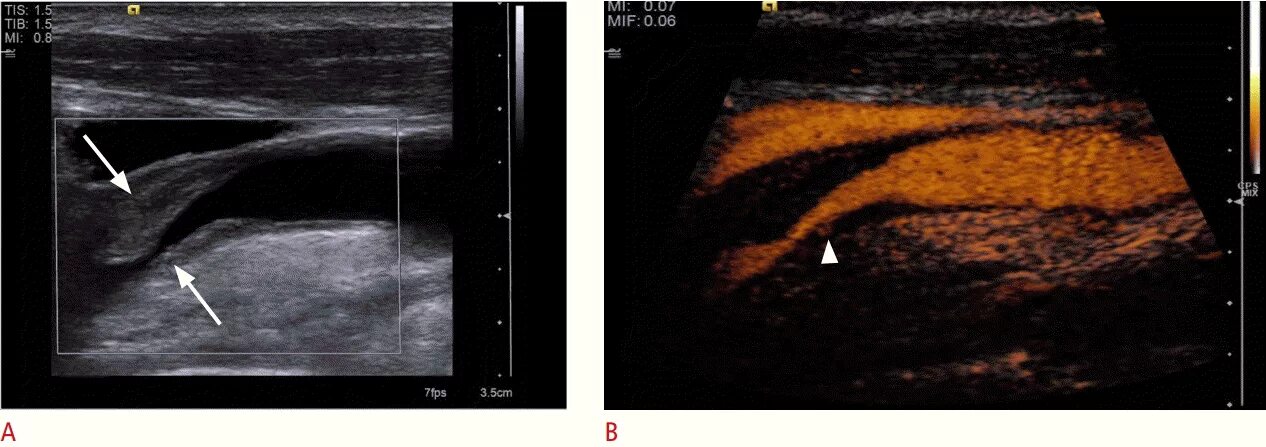

Атеросклеротическая бляшка узи